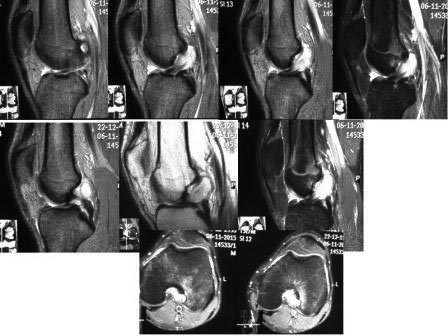

по Вашим снимкам нельзя ничего сказать. Лучше выложите снимки на диске

Да. Обсуждать можно только полную электронную выкладку МРТ. Как-то 9 из 200-300 сканов обсуждать неправильно...

Михаил, а Вы сами смогли по представленным Вами снимкам что-то сказать?

Единственное, что я могу по ним сказать с уверенностью, что есть дисплазия мыщелков бедра и есть латеральный подвывих надколенника, есть отек кости на наружном мыщелке бедра в месте инсерции ПКС. Каких-либо тонкостей по наличию повреждений структур сустава я лично разглядеть не могу.

Вид ПКС смущает. Проверьте еще раз внимательно все тесты на несостоятельность ПКС (передней выдвижной ящик при разных углах сгибания, Лахмана, пивот-шифт тест).

Обращает на себя внимание латерализация надколенника. Возможно, мы имеем дело с синдромом латеральной гиперпрессии надколенника.

Изменения в ПКС есть, это видно, если рассмотреть с увеличением. Волокна не прослеживаются, формируется опухолевидное образование.

Нет ли здесь онкологии?

Возможно киста ПКС.